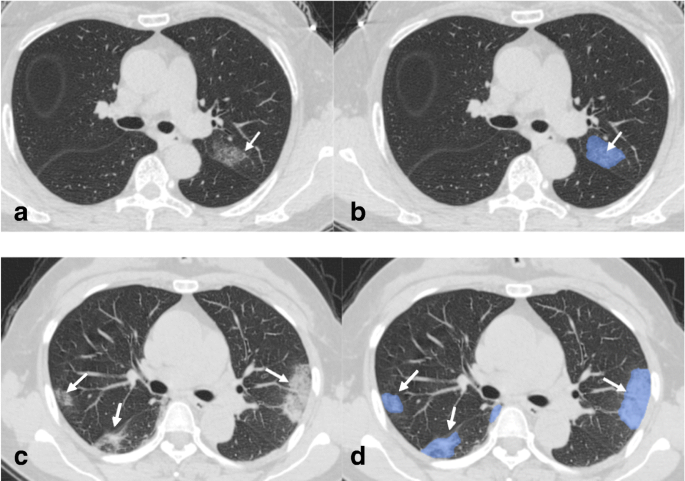

Transverse Thin Section Ct Scans In Medical Staffs Infected With Download Scientific Diagram